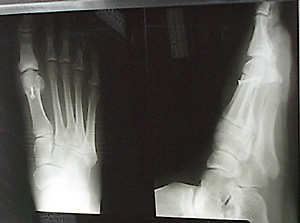

I went through

the proper steps and made an appointment with Dr. Seel. He poked and prodded,

then took some x-rays.

The joint and

bone were pretty messed up. (Rolling a piano over my toe 20 years ago

probably did not help.) We discussed my options and surgery promised the

best resolution.

Dr.

Seel had cut through the tarsal bone near the base of my great right toe

on a "V" shaped angle. That is to say, he chopped off my big toe.

He cleaned up the joint, removed the overgrowth on the tarsal and lowered

it to correct the cause of the malformation. He repaired the severed bone

with a screw-like device. |